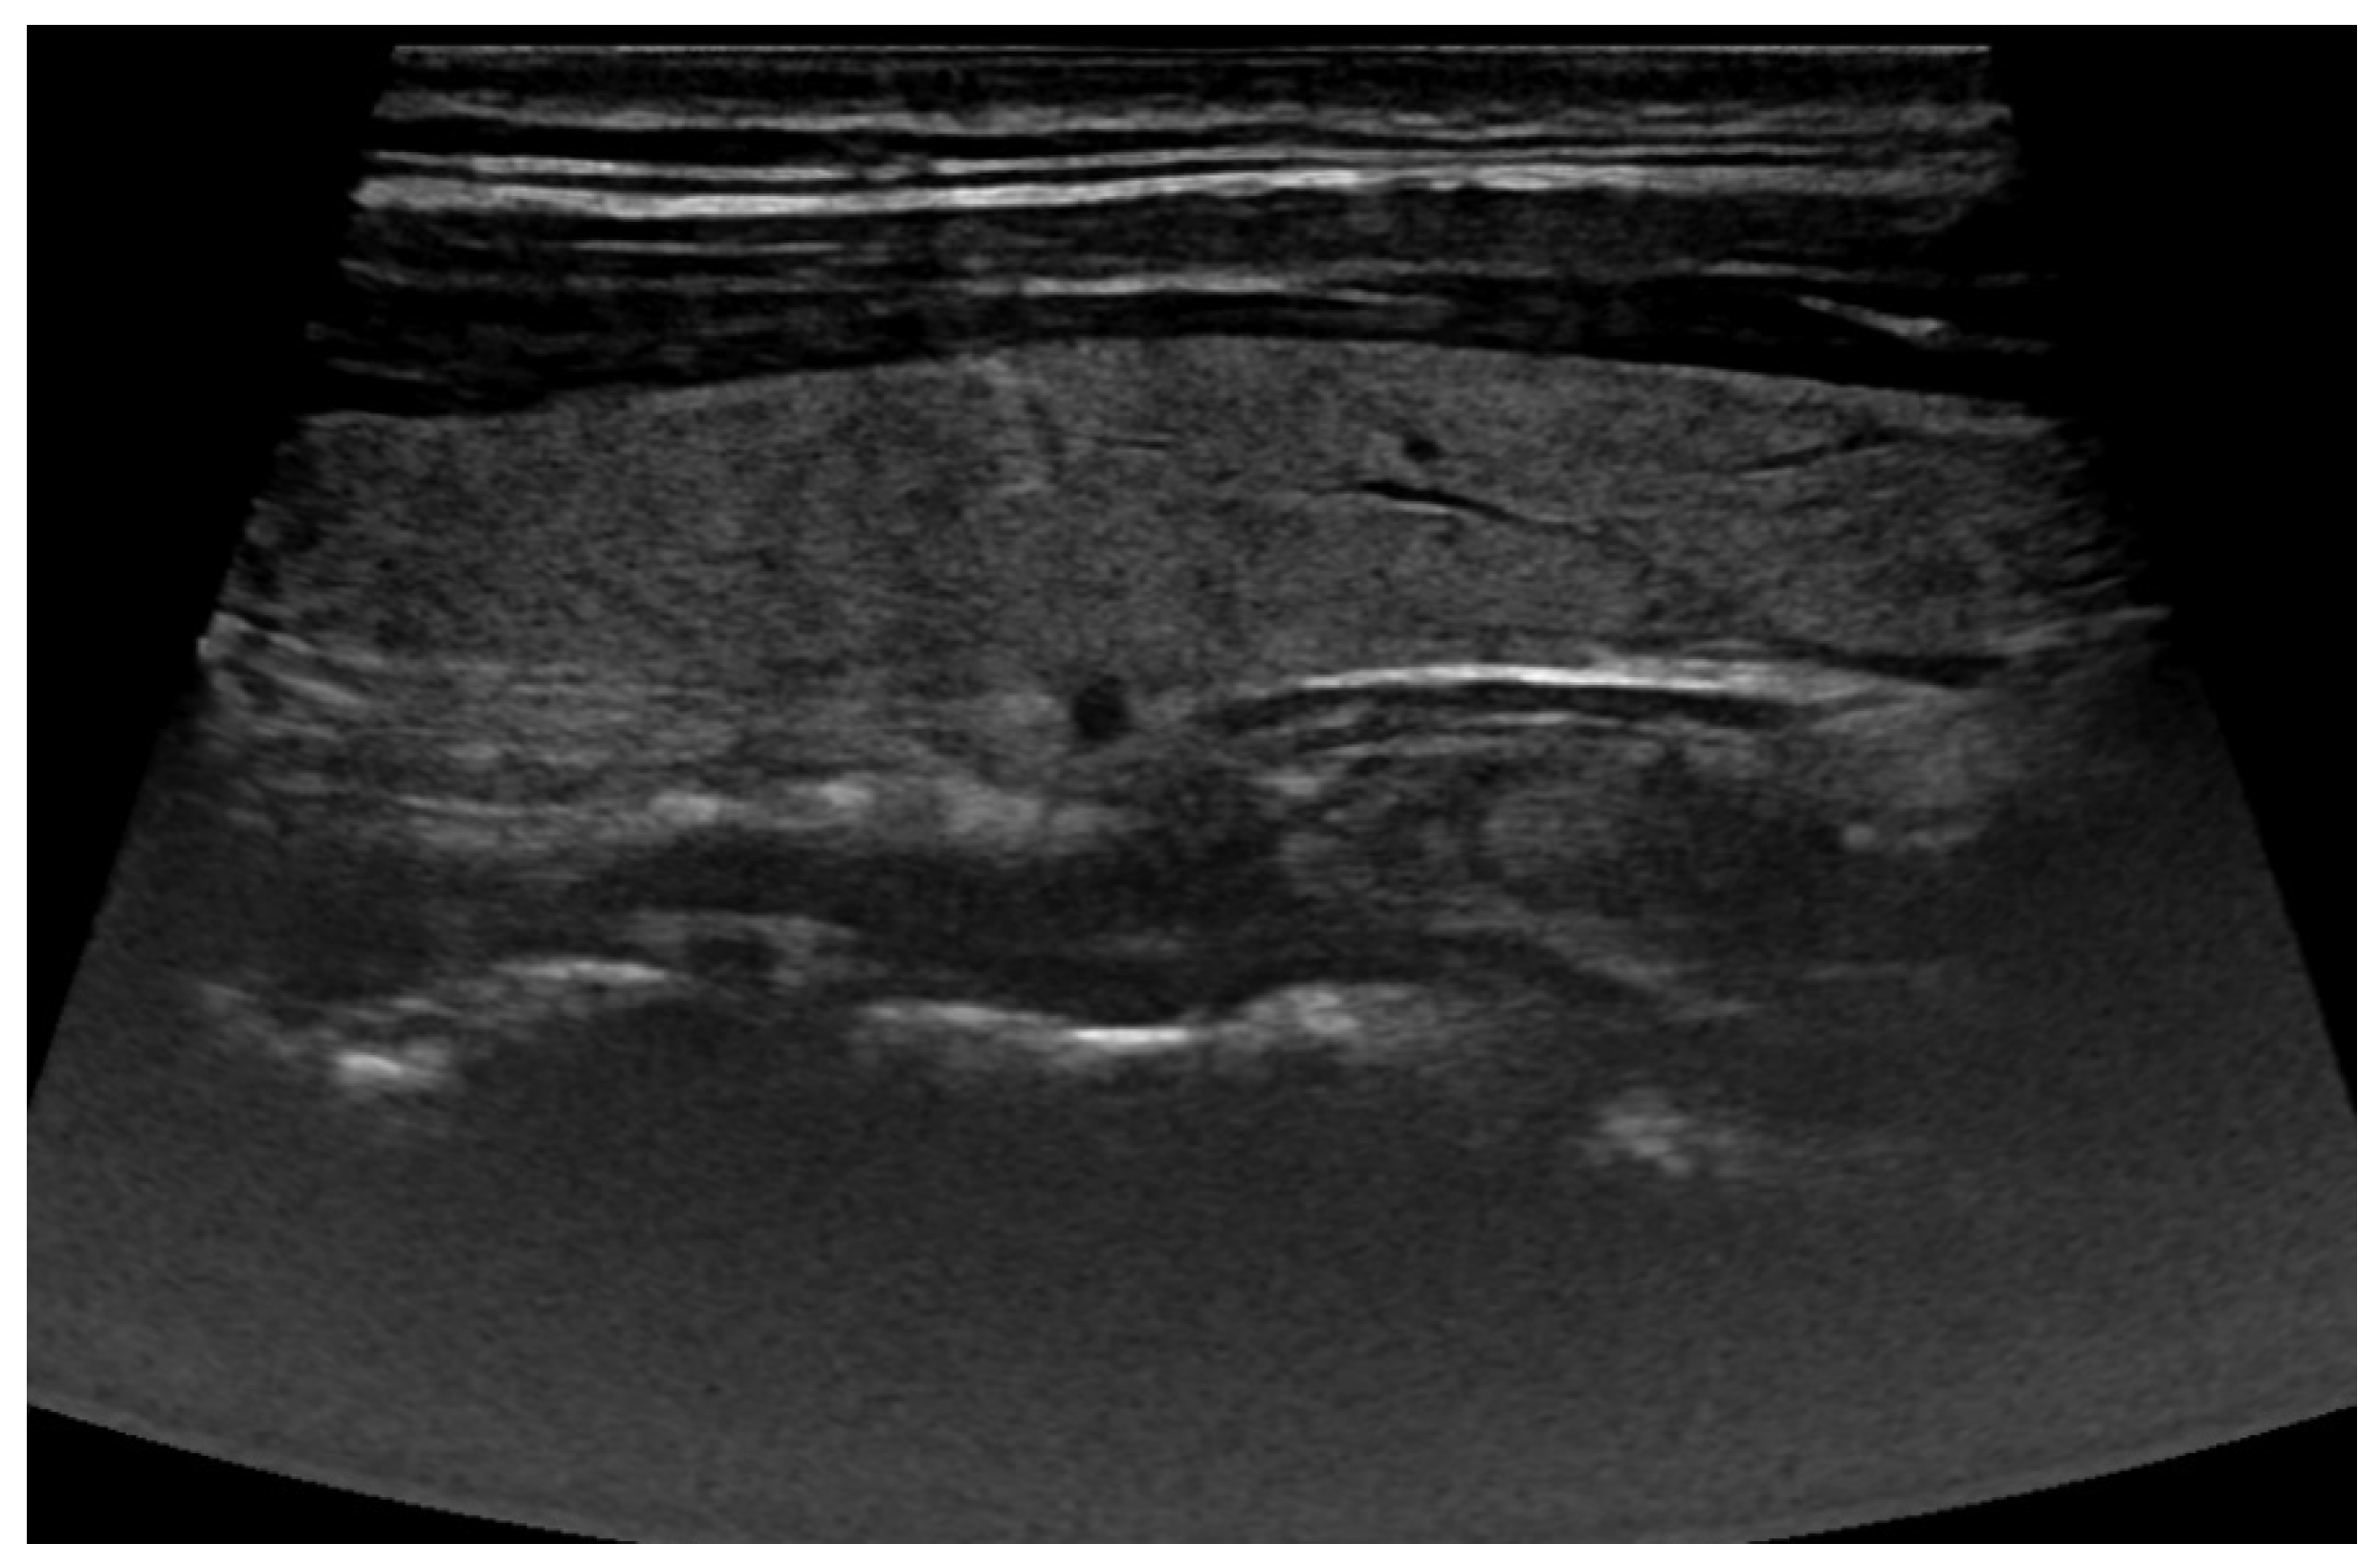

2.1. Ultrasound Images

3.1. Thyroid Nodule Diagnosis Based on Ultrasound Images: Binary Classification Problem Solved Using Convolutional Neural Networks